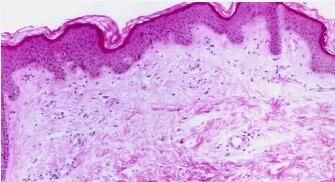

慢性荨麻疹怎么预防?我们周围有很多人被慢性荨麻疹所困扰,常常会问这个问题。但目前有很多患者对慢性荨麻疹了解不足,错过了较佳治疗时机,从而导致病情发展严重。其实在日常生活中只要了解慢性荨麻疹,就可以更早的发现以及治疗慢性荨麻疹,从而降低给我们带来的影响。及时发现慢性荨麻疹,及时治疗,才可以减少皮肤损伤。知道慢性荨麻疹的病因,就可以及时预防慢性荨麻疹。

慢性荨麻疹怎么预防?北京京城皮肤医院指出,荨麻疹病因复杂,致敏源广泛。明确病因是避免复发的关键,对无法避免的致敏源可给予脱敏治疗或预防性服药。根据不同的类型选用不同的治疗方案。急性荨麻疹尤其是伴有全身症状者应及时就诊,慢性患者可使用多联诊疗或长期用药逐渐减量,尽量使用较小维持量。慢性荨麻疹预防可选用2-3种抗组胺类药物联合或交替使用,病情控制后渐减量至停,也可试用封闭诊疗、自血诊疗、针刺诊疗、氧气诊疗、组织诊疗。